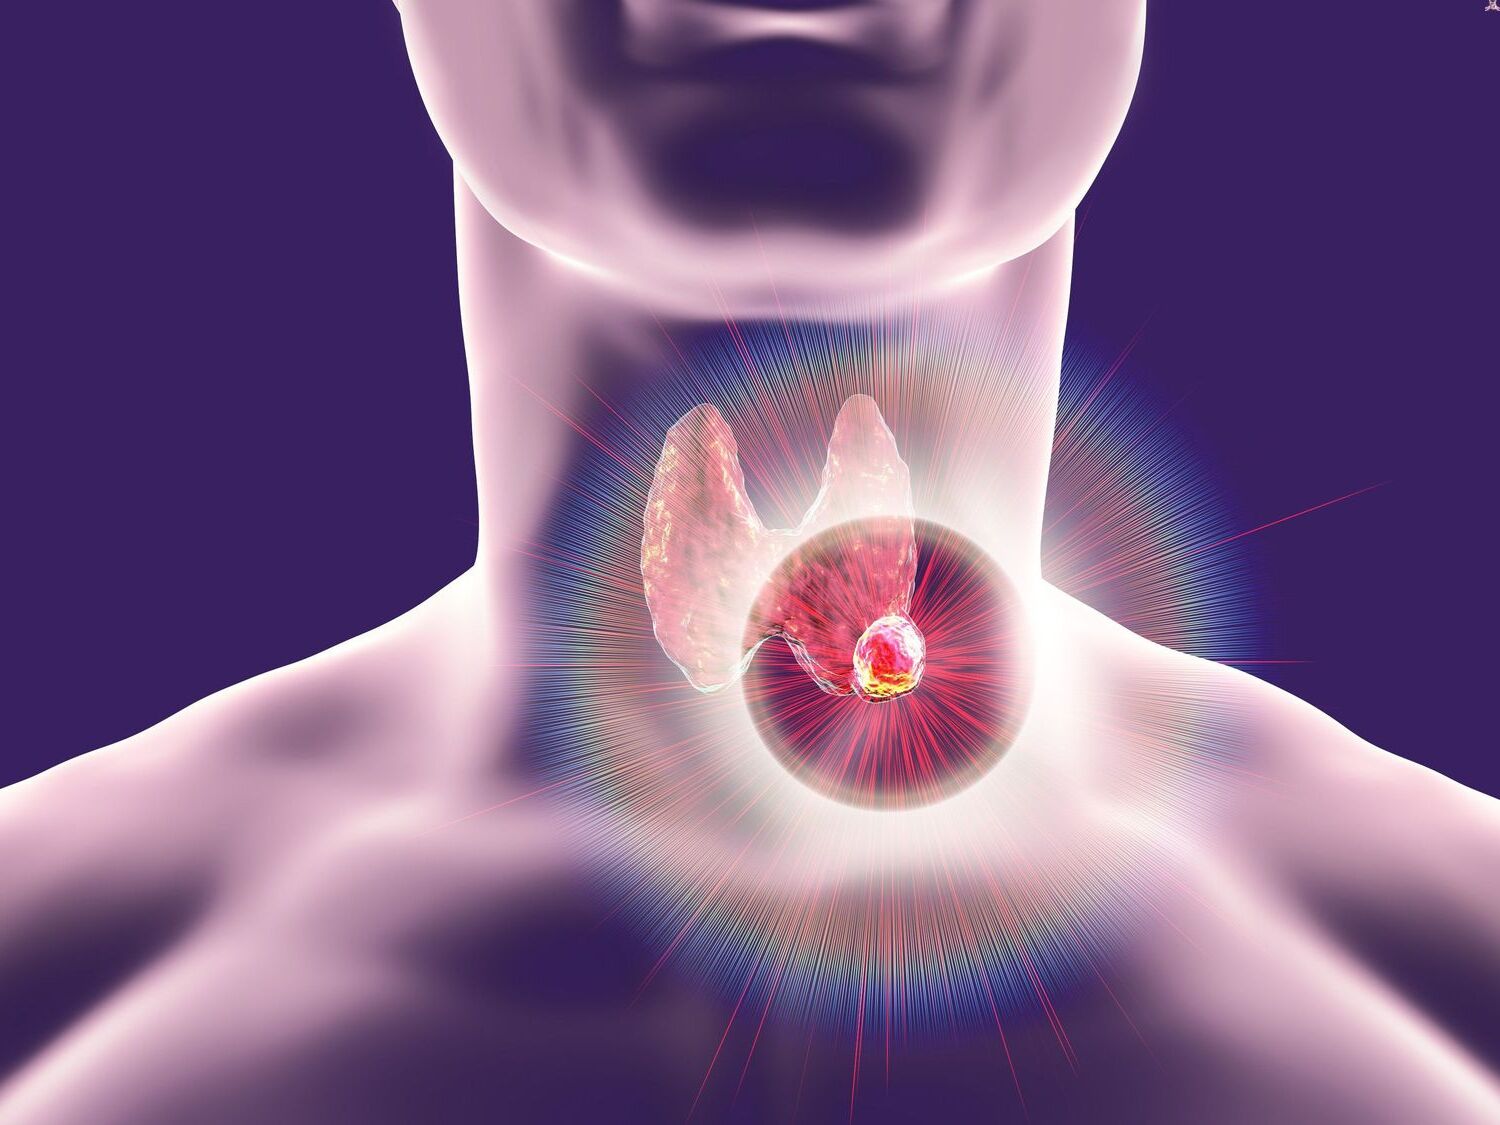

20 Best Facts About Thyroid Cancer Facts

https://facts.net/wp-content/uploads/2024/06/20-best-facts-about-thyroid-cancer-1718817819.jpg